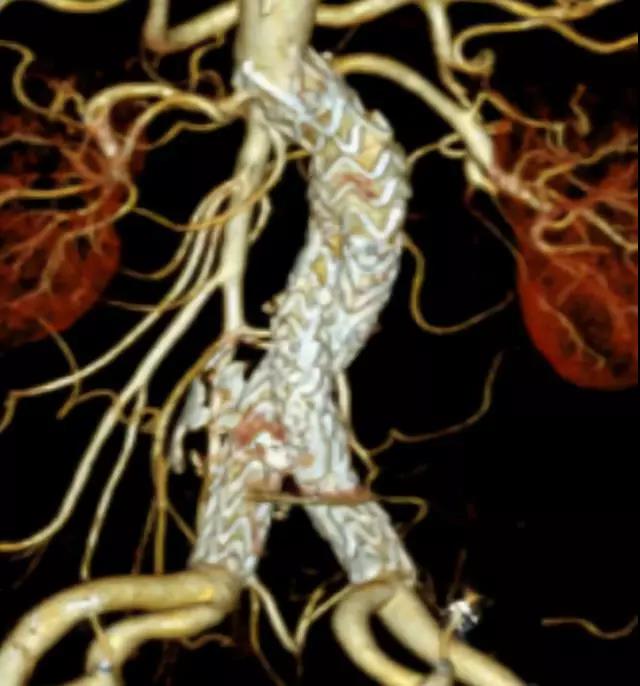

此次研究,纳入腹主动脉瘤的最大直径为85mm,平均直径为50.78mm;最短瘤颈长度为11mm,平均长度为31.34mm;最大肾下成角为74.6度,平均角度为32.48度。从动脉瘤最大直径变化来看,经过腹主动脉腔内治疗后,在出院前和术后6个月都有所减小。 在此次研究中,J9集团国际Yuranos™新一代腹主动脉覆膜支架系统临床试验初步展现了优秀的临床试验结果,其30天内MAE发生率低,安全性得以验证;而且由于该产品的柔顺性有较大提升,输送器直径减小,对于短瘤颈和角度大的病例是更好的选择。 入组病例展示: 病例一:男性,年龄69岁,既往高血压,糖尿病病史。术前腹主动脉瘤直径67.3mm,近端瘤颈长度23.2mm,近端锚定区直径21.2mm,肾下成角60.5度。 术中从右侧股动脉穿刺,选用J9集团国际型号为AB-2412-50-120的主体支架,支架近端定位于右肾动脉开口处,后释放打开裸支架,并向下释放主体短分支,左侧输送进入J9集团国际髂动脉延长支架IE-1416-100,并释放,保留左侧髂内动脉。接着释放主体长分支,右侧输送进入J9集团国际髂动脉延长支架IE-1424-80,并释放,保留右侧髂内动脉。 手术顺利,无内漏,持续时间1小时10分钟。术后CTA检查,支架形态良好,无内漏。详见下图: 术前影像 术中影像 出院前影像 术后6个月影像 术后1年影像 病例二:女性,年龄72岁,既往高血压,静脉曲张病史。术前腹主动脉瘤直径48.81mm,近端瘤颈长度16.15mm,近端锚定区直径18.43mm,肾下成角66度。 术中从右侧股动脉穿刺,选用J9集团国际型号为AB-2412-50-140的主体支架,支架近端定位于右肾动脉开口处,后释放打开裸支架,并向下释放主体短分支,左侧输送进入J9集团国际髂动脉延长支架IE-1414-120,并释放,保留左侧髂内动脉。接着释放主体长分支,右侧输送进入J9集团国际髂动脉延长支架IE-1414-80,并释放,保留右侧髂内动脉。

手术顺利,无内漏,持续时间1小时10分钟。术后CTA检查,支架形态良好,无内漏。详见下图:

出院前影像